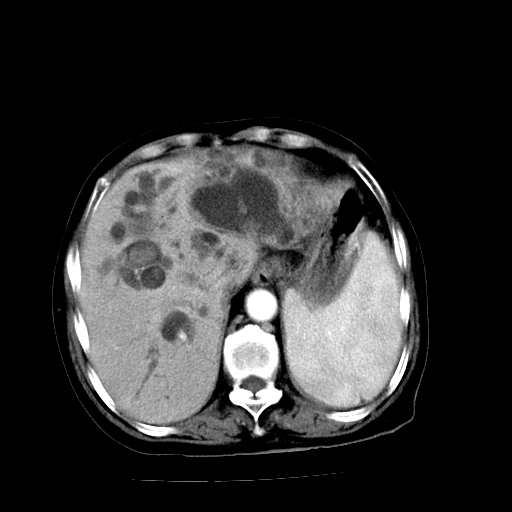

以下是引用随光逐影在2009-4-7 8:21:00的发言:[br]肝内外胆管多发性结石并肝内外胆管扩张;胆系感染。